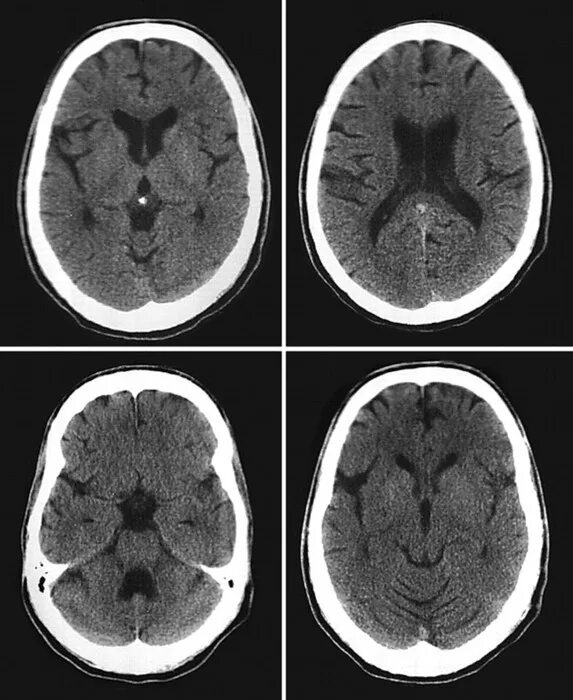

Норма кт